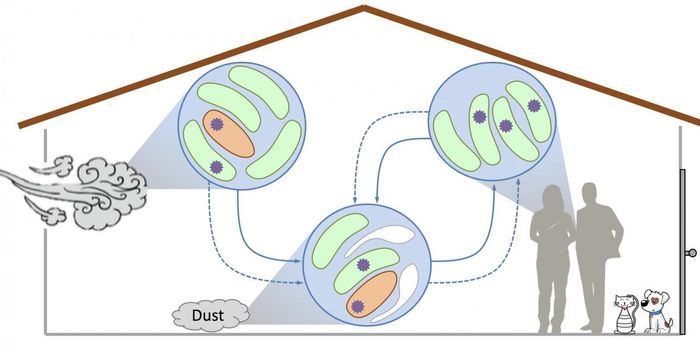

AUG 05, 2021ImmunologyTalking, singing, coughing—all of these can spread COVID-19 from an infected person via respiratory aerosols. Thes ...